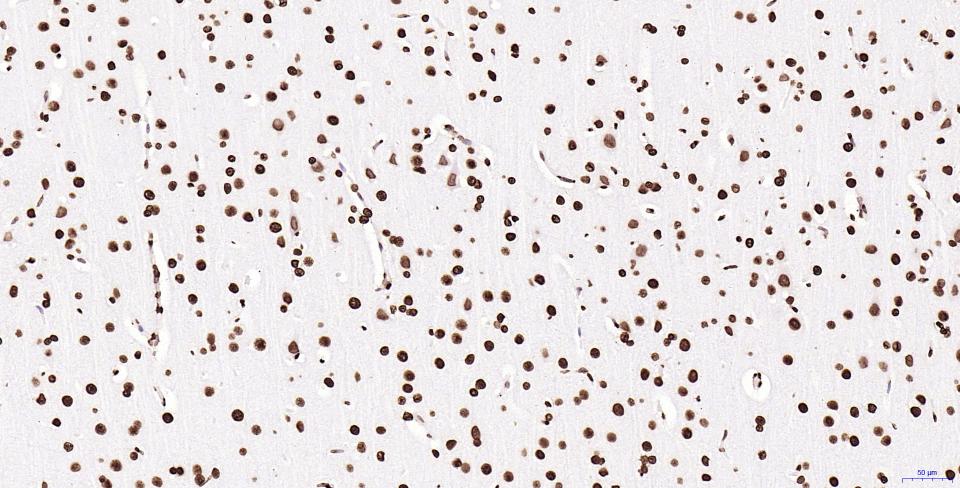

Paraformaldehyde-fixed, paraffin embedded Mouse Cerebrum; Antigen retrieval by boiling in sodium citrate buffer (pH6.0) for 15 min; Antibody incubation with Histone H2A.X Monoclonal Antibody, Unconjugated(bsm-61080R) at 1:200 overnight at 4°C, followed by conjugation to the SP Kit(Rabbit, SP-0023) and DAB (C-0010) staining.